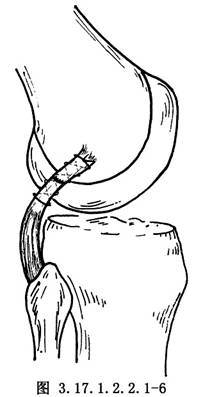

如半月板和交叉韌帶有損傷,儘可能予以修補,然後再自後側開始修補外側結構。①如有後外側關節囊撕脫,將其牽到脛骨關節面下方,用圓針引絲線穿過脛骨關節面下的鑽孔,由前到後縫合固定在脛骨上(圖3.17.1.2.2.1-4)。固定前將脛骨附着部的骨表面弄毛糙,或用骨刀做一新鮮骨創面,以保證後外側關節囊的固定。②有膕肌腱撕裂者,按損傷類型採用不同的方法。股骨附着部的膕肌腱撕裂,常伴有外側副韌帶自股骨上撕脫,可採用Bunnell縫合,通過股骨的鑽孔,捆紮在股骨內上髁的骨面上(圖3.17.1.2.2.1-5)。膕肌腱本身撕裂,將兩端用Bunnell縫合(圖3.17.1.2.2.1-6)。撕裂在肌肉內或肌腱連接部,用Bunnell縫合通過脛骨前外側近端Gerdg結節的骨孔,將肌腱附着到脛骨的後面(圖3.17.1.2.2.1-7)。③修補外側副韌帶。對外側副韌帶的撕裂先明確撕裂的部位,對股骨附着部的撕脫可採用U形釘、螺釘固定,或將斷端用Bunnell縫合,通過股骨的鑽孔捆紮在股骨內上髁上。外側副韌帶從腓骨頂點撕裂則伴有股二頭肌腱、弓狀韌帶及腓側副韌帶附着點的複合撕脫,應一併修復,在腓骨頭穿孔,粗線縫合固定。伴有骨片撕脫,可用1枚螺釘或交叉克氏針固定骨片(圖3.17.1.2.2.1-8)。如爲韌帶本身的撕裂,找出兩斷端拉緊後屈膝30°位,用不吸收的絲線對端或重疊縫合(圖3.17.1.2.2.1-9)。並將外側緣向前推進,縫合在外側正中關節囊的後緣和外側副韌帶的後緣。還可應用股二頭肌腱、腓腸肌腱和髂脛束加強修補。